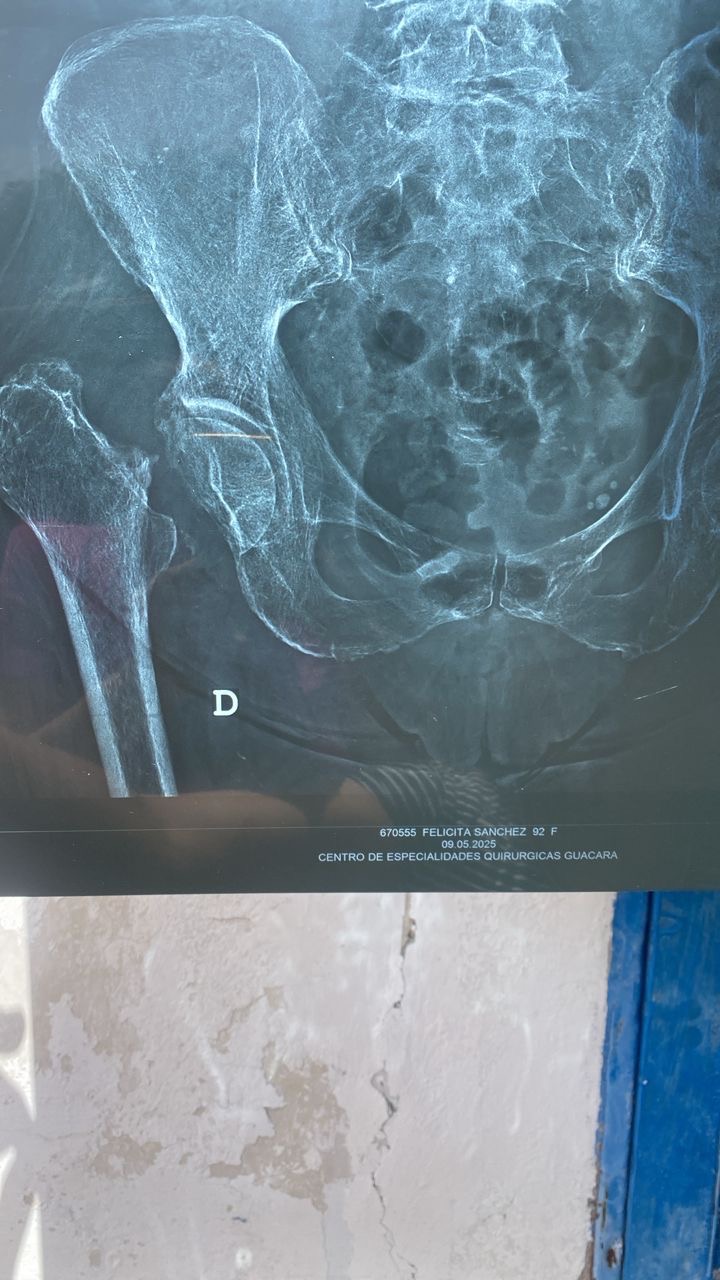

Recientemente sufrió una fractura de fémur, lo que ha limitado completamente su movilidad y le ha generado un dolor constante. El diagnóstico médico es claro: necesita una operación urgente para colocar una prótesis de reemplazo articular. Esta cirugía es fundamental para que pueda volver a caminar, aliviar el dolor y mejorar significativamente su calidad de vida.